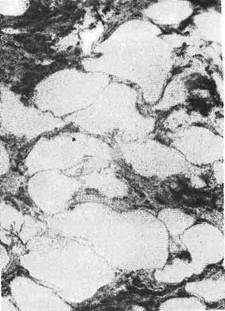

Рис. 341. Изменения селезенки при

крупноочаговой генерализации гемато-

генного туберкулеза.

Наконец, в некоторых случаях

наблюдается острый об-

щий крупноочаговый

туберкулез, который встре-

чается обычно у ослабленных

больных и характеризуется об-

разованием в разных органах

крупных (диаметром до 1 см)

туберкулезных очагов (рис. 341)